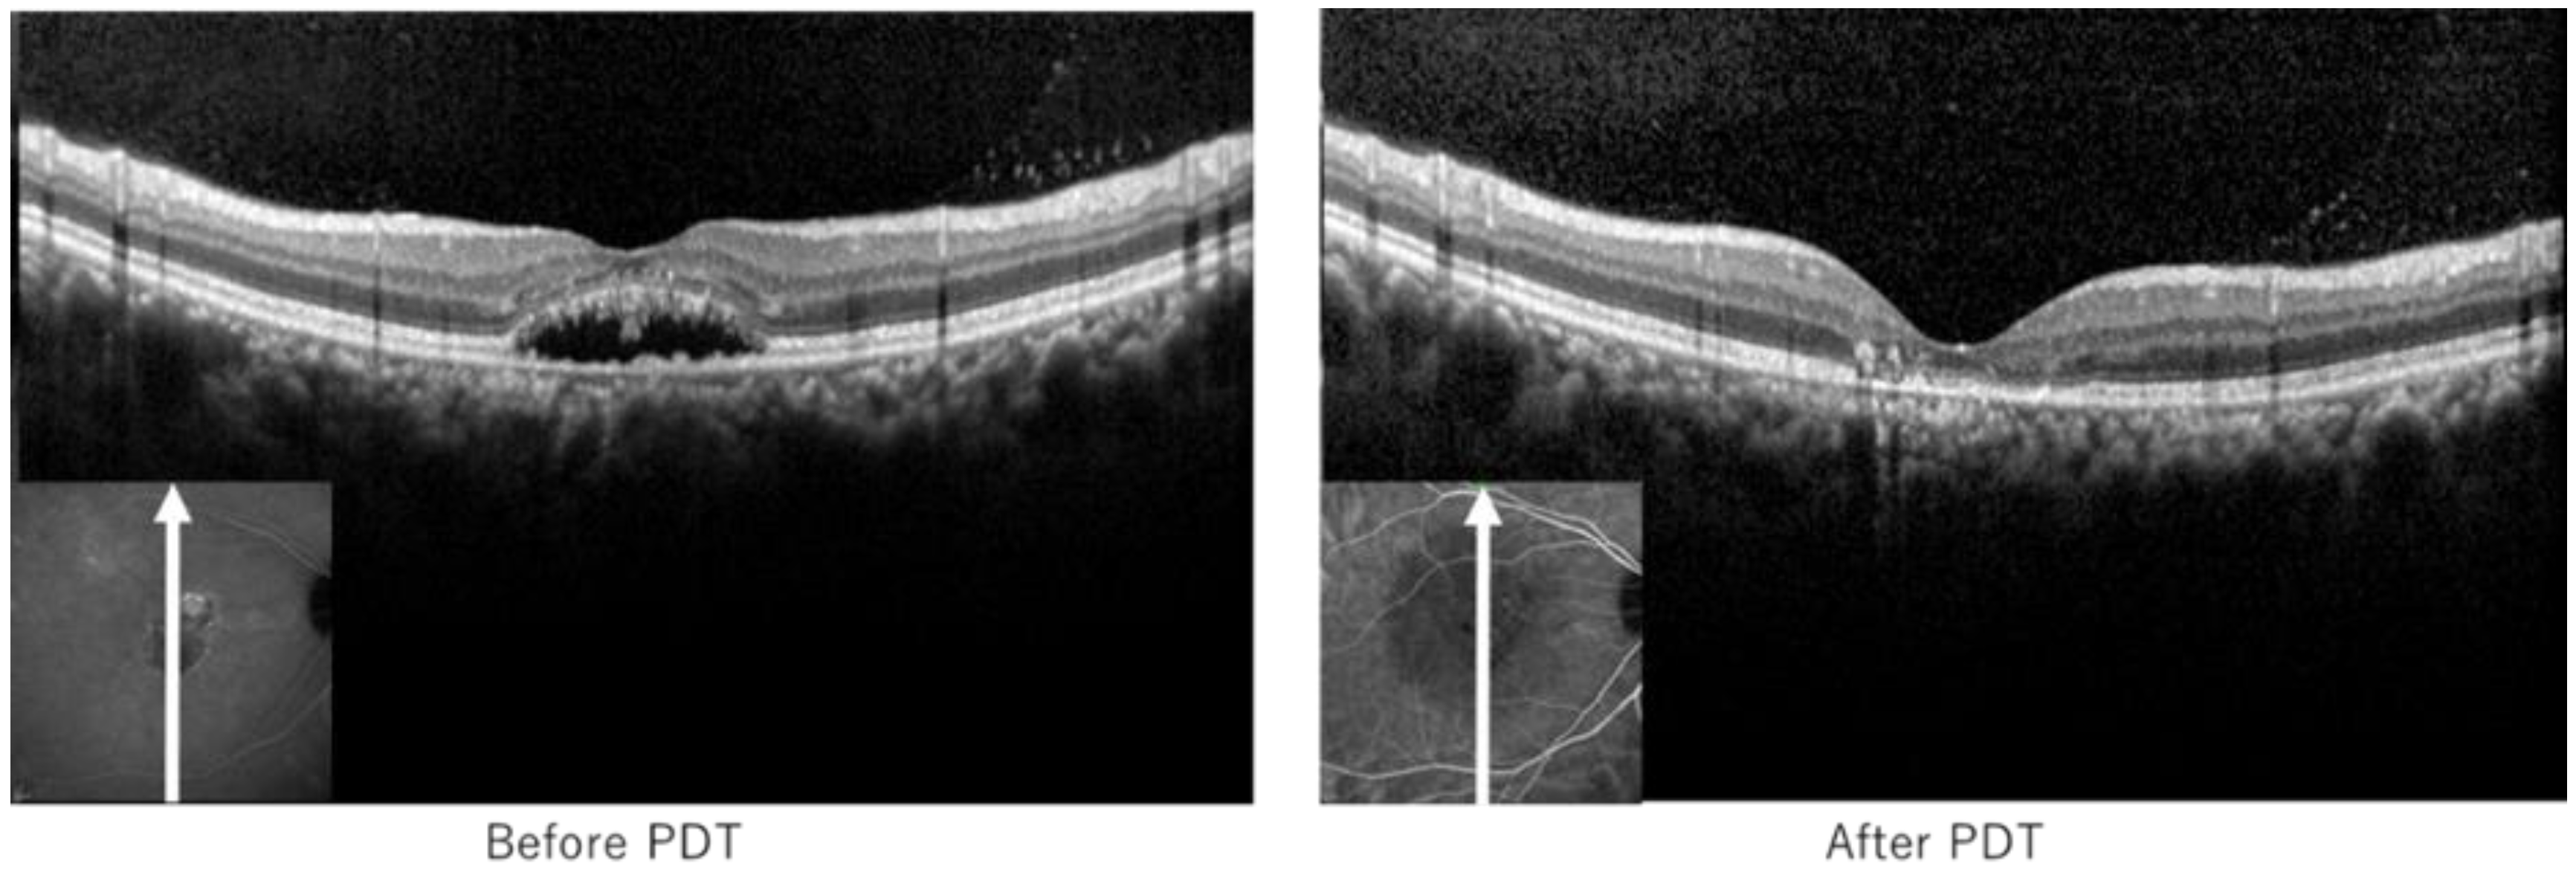

3.3. Representative Case